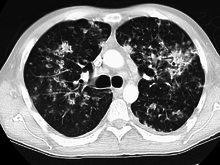

Miliary tuberculosis is a form of tuberculosis that is characterized by a wide dissemination into the human body and by the tiny size of the lesions (1–5 mm). Its name comes from a distinctive pattern seen on a chest radiograph of many tiny spots distributed throughout the lung fields with the appearance similar to millet seeds—thus the term "miliary" tuberculosis. Miliary TB may infect any number of organs, including the lungs, liver, and spleen.[2] Miliary tuberculosis is present in about 2% of all reported cases of tuberculosis and accounts for up to 20% of all extra-pulmonary tuberculosis cases.[3]

Testing for miliary tuberculosis is conducted in a similar manner as for other forms of tuberculosis, although a number of tests must be conducted on a patient to confirm diagnosis.[5] Tests include chest x-ray, sputum culture, bronchoscopy, open lung biopsy, head CT/MRI, blood cultures, fundoscopy, and electrocardiography.[11] The tuberculosis (TB) blood test, also called an Interferon Gamma Release Assay or IGRA, is a way to diagnose latent TB. A variety of neurological complications have been noted in miliary tuberculosis patients—tuberculous meningitis and cerebral tuberculomas being the most frequent. However, a majority of patients improve following antituberculous treatment. Rarely lymphangitic spread of lung cancer could mimic miliary pattern of tuberculosis on regular chest X-ray. [16]